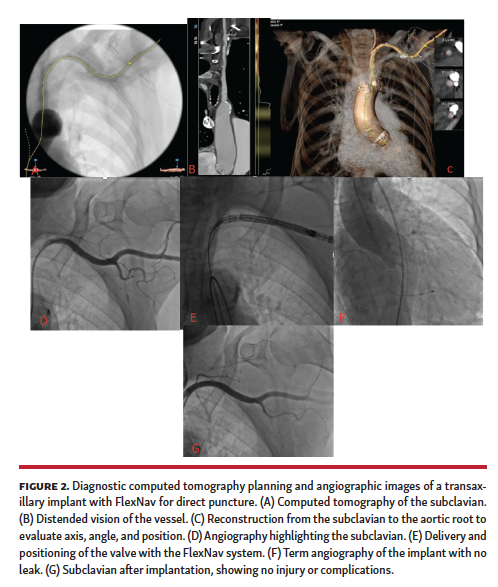

The landscape of structural heart disease is expanding momentously, with novel devices being introduced almost every month for mitral or tricuspid valve disease.16 In this setting, TAVI represents a pioneering intervention for valve disease. Despite being relatively young (at least in comparison with percutaneous coronary intervention), TAVI has already met many seminal milestones, such as toppling the role of medical therapy in patients with absolute contraindications to surgery and actively challenging SAVR in subjects at intermediate-to-high surgical risk.1,2 Despite these successes, the activation and implementation of a TAVI program remains challenging, given the multidimensional challenges faced by invasive cardiologists as well as surgeons (Figures 1-3).17 A key factor to consider is the availability of several TAVI devices, each with its own strengths, weaknesses, and subtleties. Furthermore, device improvements are often provided, which may (hopefully favorably) shift the overall risk-benefit profile of the product.18

We hereby present our clinical experience with the novel FlexNav delivery system for Portico valve implantation in patients undergoing TAVI at our institution in early 2020.10,11 This delivery system is characterized by small size, hydrophilic coating, and controlled release function, thus expanding the indications of TAVI with Portico, and increasing the safety and ease of the procedure. In our case series, we did not recognize any meaningful risk of suboptimal control due to a potential “slipperiness” of the overall system. Moreover, we found that the new delivery system did not intuitively influence the properties of the valve, but allowed a better, more precise delivery and enhanced the eventual procedural result. Furthermore, the new delivery system is easy to handle and offers a series of qualities useful for the operator. There is also greater stability and improved flexibility compared with the previous generation of the delivery system. Among the cases treated, 2 patients had a calcified and tortuous aortoiliac axis, such as to complicate the transition from the iliac tract to the abdominal aorta. In such patients, without the need to upgrade guidewire stiffness, it was possible to overcome the challenging anatomy through a counter-clockwise rotation, thanks to the hydrophilicity of the device. Similarly, in cases treated with transaxillary access, the device behaved favorably by gaining access without the introducer, and by maintaining stability during valve implantation.